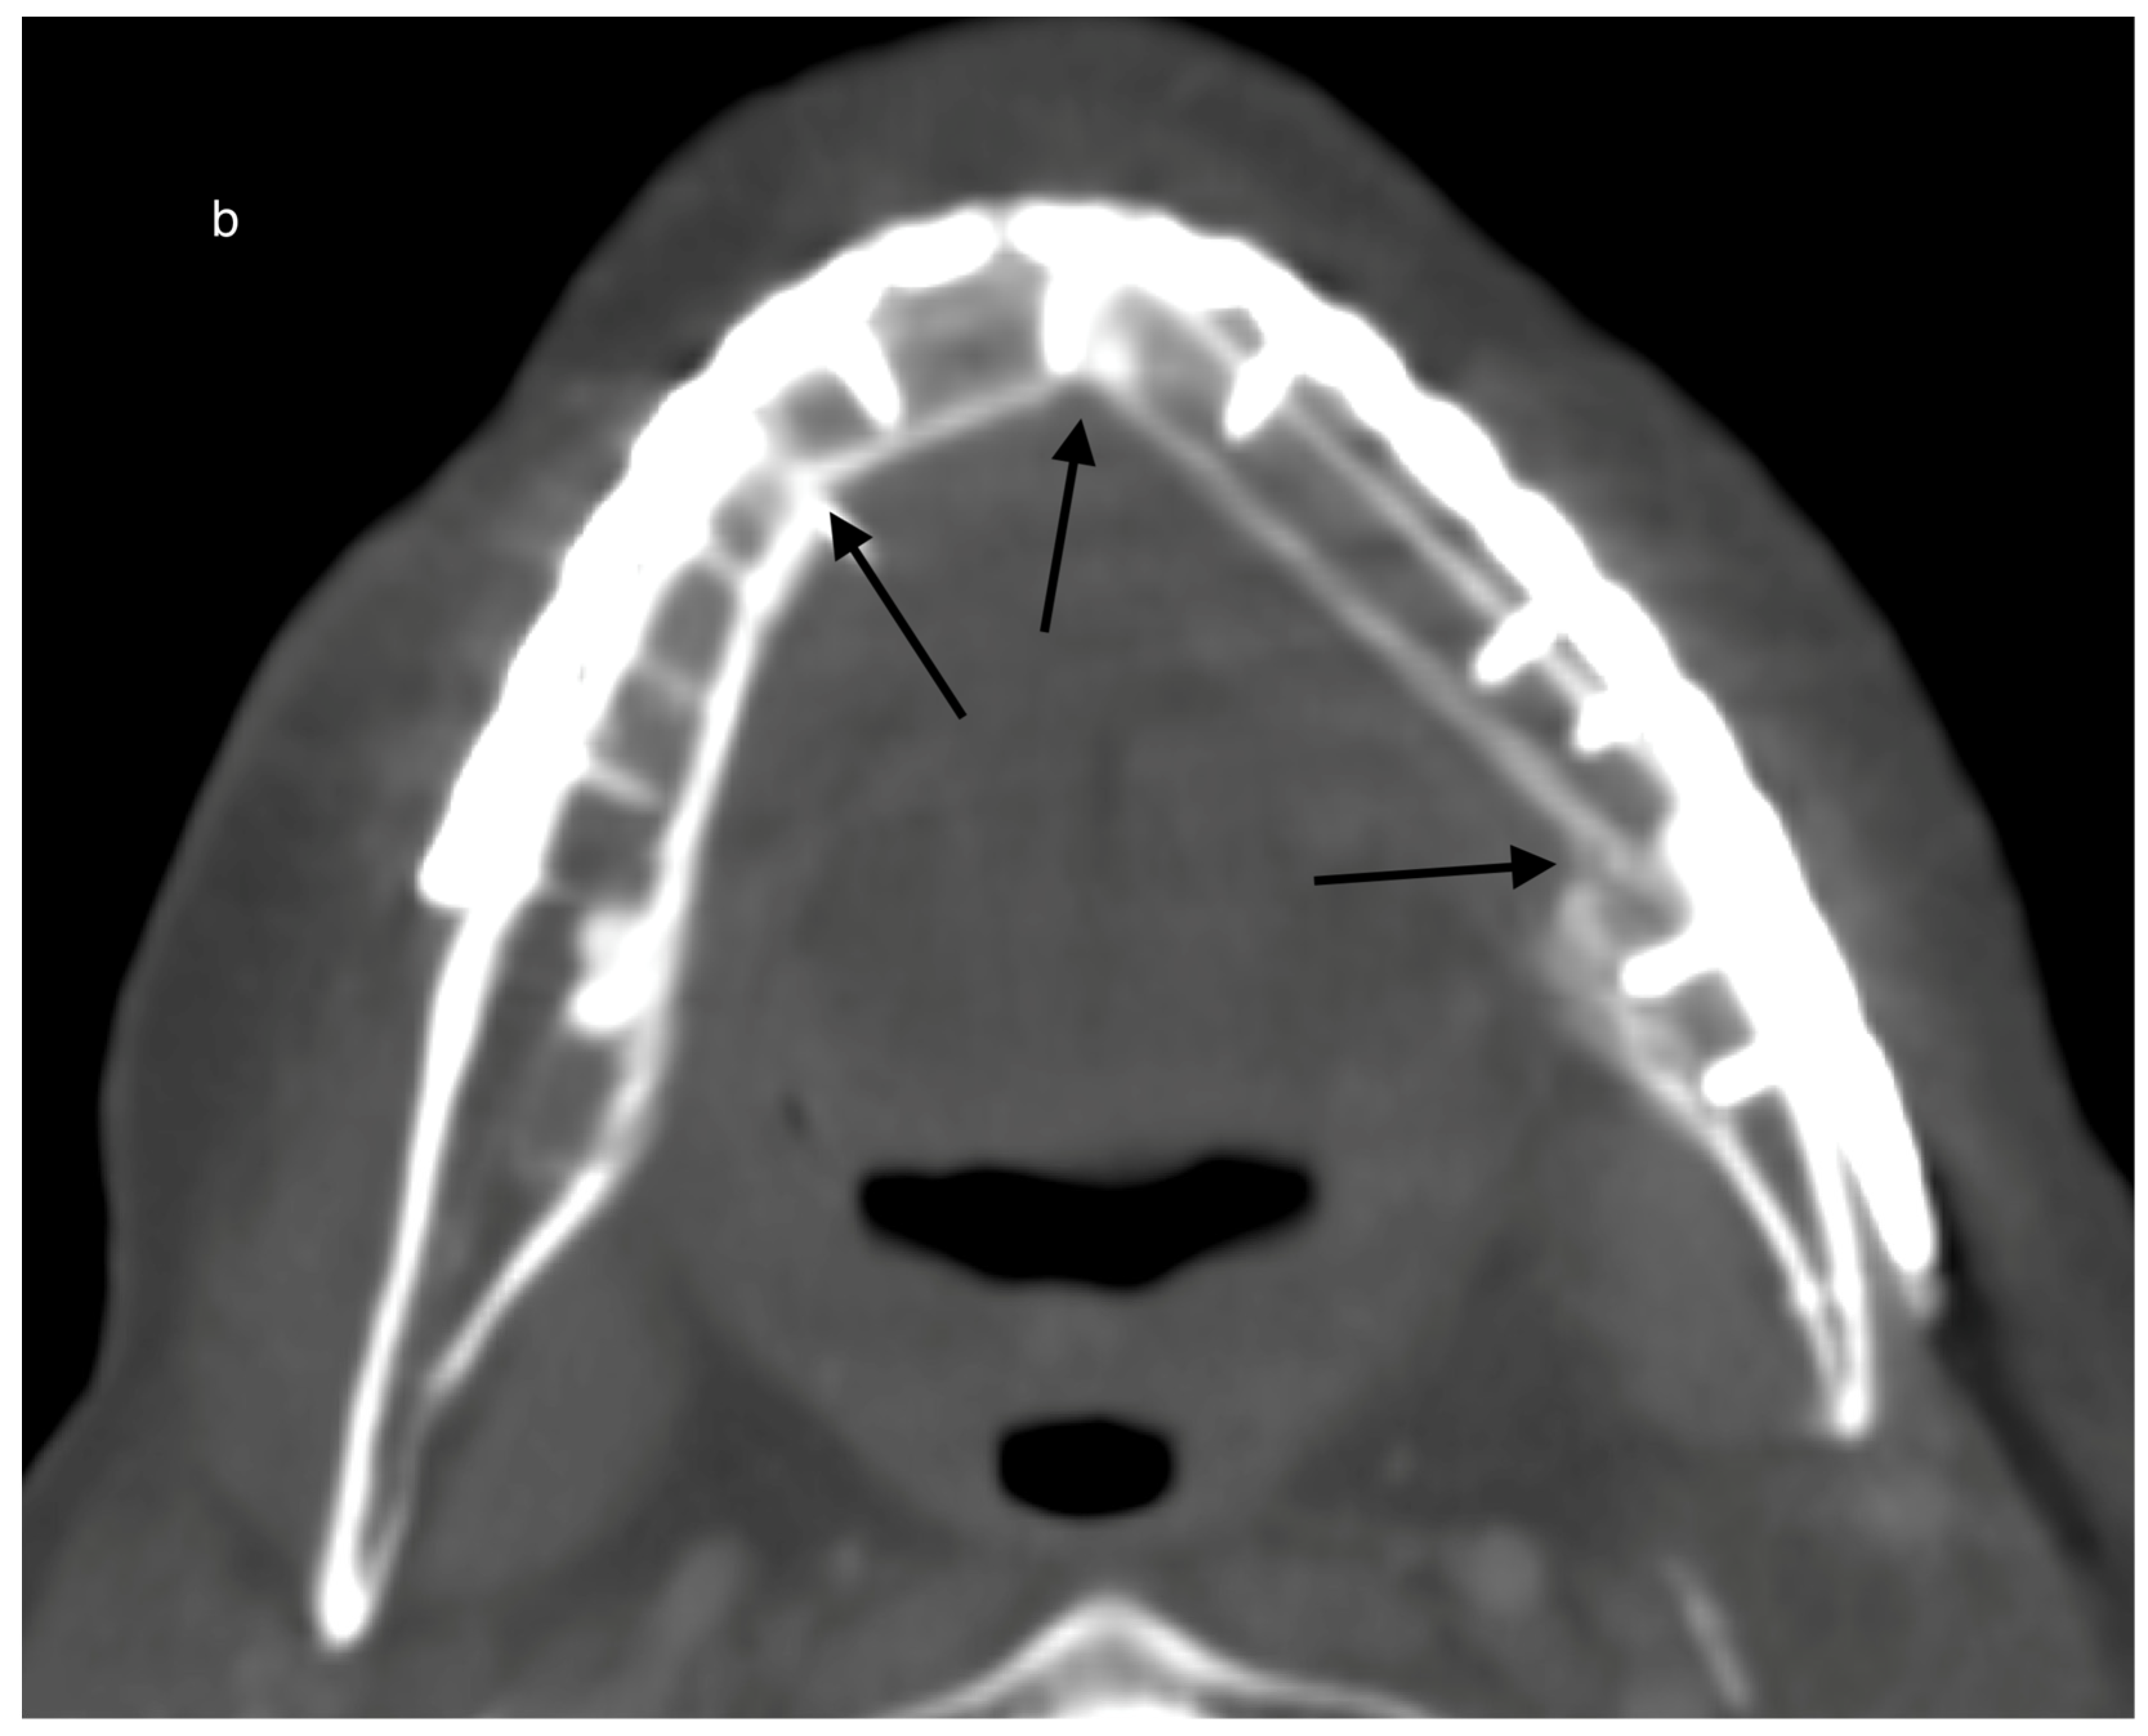

Figure 4.

Example for ossification in CT scans over time in a case with a primary reconstructed mandible after malignant tumor resection and post-reconstructive adjuvant radiotherapy (postORT): Example for a reconstructed mandible with a 2-segmented fibula 265 days after operation. All three contact points are marked with black arrows (a). Slow progression of ossification (black arrows) after 494 days (b).